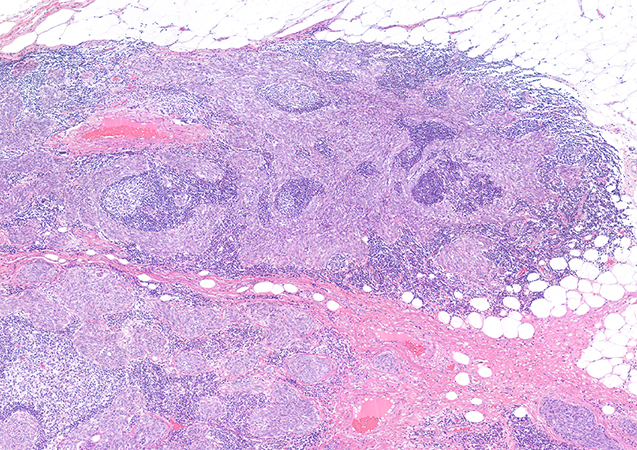

Clinical History:A 76-year-old woman presented to the emergency department with acute chest pain associated with hypertensive crisis and flushing. A thoracic computed tomography (CT) scan revealed a 22-mm nodule in the anterior mediastinum. The lesion was surgically excised shortly thereafter. On gross examination, the specimen consisted of a well-circumscribed, solid-cystic whitish lesion. Histopathological findings on hematoxylin and eosin staining are shown in Figures 1 and 2. Immunohistochemical results are presented in Figure 3 (p40), Figure 4 (CD5), Figure 5 (c-KIT), and Figure 6 (TdT). Neoplastic cells were negative for neuroendocrine markers, PAX8, and Epstein-Barr virus (EBV).

Micronodular thymic carcinoma with lymphoid stroma (MTCLS) is a rare thymic epithelial tumor, provisionally classified as a subtype of thymic squamous cell carcinoma (SCC) in the 2021 WHO classification. It is characterized by multiple small epithelial nodules separated by abundant lymphoid stroma with reactive germinal centers, a pattern that closely mimics micronodular thymoma with lymphoid stroma (MTLS). In our case, the hematoxylin and eosin sections (Figures 1 and 2) demonstrate well-defined micronodules of tumor cells with cytologic atypia, including vesicular nuclei, prominent nucleoli, and scattered mitoses. The lymphoid background is reactive and polyclonal, with well-developed germinal centers and TdT-negative mature lymphocytes, unlike conventional thymomas where TdT-positive immature T cells are present. Immunohistochemistry was key to the diagnosis. The tumor cells co-expressed CD5 and c-KIT (CD117) (Figures 4 and 5), a profile typical of thymic carcinoma and not seen in thymomas. They were negative for PAX8 and neuroendocrine markers, helping to exclude metastatic carcinoma and neuroendocrine tumors. TdT was negative in the lymphoid stroma (Figure 6), confirming its mature, reactive nature.